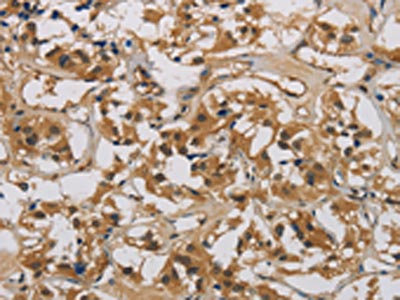

• The image is immunohistochemistry of paraffin-embedded Human gastric cancer tissue using CSB-PA785649(CASP9 Antibody) at dilution 1/70. (Original magnification: ×200)

• The image is immunohistochemistry of paraffin-embedded Human thyroid cancer tissue using CSB-PA785649(CASP9 Antibody) at dilution 1/70. (Original magnification: ×200)